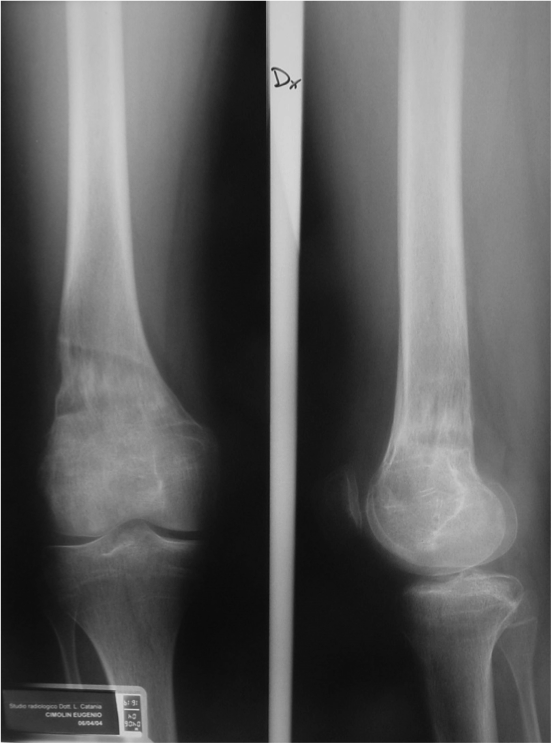

Risultato radiografico

Folow up clinico e radiografico a 3 anni